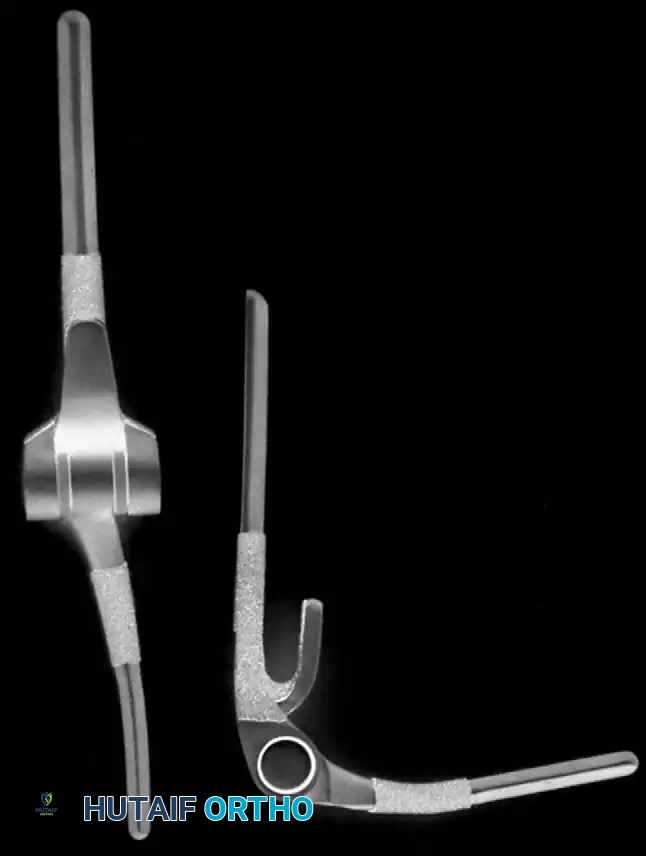

- Semiconstrained Metal-to-Polyethylene Hinges: Implants such as the Mayo, Coonrad-Morrey, GSB III, and Discovery designs incorporate a "sloppy hinge." This design allows 7 to 10 degrees of varus-valgus and rotational laxity, dissipating stresses away from the cement-bone interface and into the surrounding soft tissues.

- Unconstrained Resurfacing Arthroplasties: Implants like the Ewald capitellocondylar, Kudo, and Souter-Strathclyde rely entirely on intact capsuloligamentous structures and balanced musculature for stability.

Modern semiconstrained implant design.

Modern unconstrained implant design.